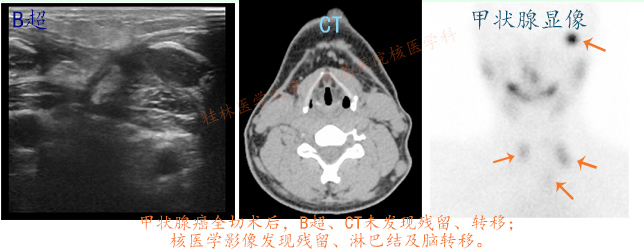

另一方面,核医学影像的灵敏度远远高于传统的B超、CT,甚至磁共振等传统影像学,因此在甲状腺癌术后行核医学甲状腺显像可以更能准确的判断是否仍存在残留,甚至可以发现CT与B超等无法判断或忽略的病灶。其中,术后的残留甲状腺是复发及转移的主要因素,尤其对于中、高危患者是不利的,影响其生存期。

甲状腺癌术后B超未见异常、CT未见异常,核医学可见残留、可见淋巴结转移、可见肺转移、脑转移等

(1)对于分化型甲状腺癌的治疗来说,手术+核医学碘131+左甲状腺素钠片是目前国际公认的三大方法,且并驾齐驱。对于甲状腺全切患者,仅以B超、CT评估残留甲状腺往往是难以得到准确信息的(正如前图所看到的)。

(2)核医学的甲状腺核素显像因其高灵敏性,可以发现传统影像不能发现的信息,这对患者的治疗效果及预后评估均有很重要的意义和价值。术后的残留多少,尤其对于中、高危患者是复发、转移的重要风险因素,亦是影响后期碘-131治疗效果的一个重要因素。因此,术后进行核医学甲状腺显像检查是有必要的,而对于有条件的患者,在术前行核医学甲状腺显像可有助于前后对比评估。